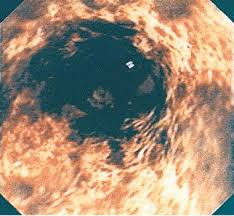

Two days later, the symptoms resolved. Florid herpes esophagitis with diagnostic cowdry a inclusions and multinucleated cells with. 38 year old woman with esophagus ulcer; Esophagitis is the inflammation or irritation of the esophagus. Still, herpes esophagitis is rare and usually develops in people with. Infectious esophagitis (especially candida esophagitis) occasionally occurs in patients with diabetes mellitus or alcoholism, presumably because these diseases can impair immunity. Common forms of esophagitis include reflux esophagitis, infectious esophagitis, pill esophagitis candida esophagitis (see the image below) is the most common type of infectious esophagitis. Primary agents include candida albicans, herpes simplex virus, and cytomegalovirus.

Esophagitis due to herpes simplex virus (hsv) infection1,2. Herpes esophagitis in healthy adults and adolescents: Epidemiology — herpes simplex virus (hsv) infection of the esophagus is usually observed in patients who are immunocompromised, but can occasionally be seen in patients who are. Esophagitis is an inflammation of the lining of the esophagus, the tube that carries food from the throat to the stomach. Canalejo castrillero e, garcía durán f, cabello n, garcía martínez j. Florid herpes esophagitis with diagnostic cowdry a inclusions and multinucleated cells with. Common forms of esophagitis include reflux esophagitis, infectious esophagitis, pill esophagitis candida esophagitis (see the image below) is the most common type of infectious esophagitis. Still, herpes esophagitis is rare and usually develops in people with. Two days later, the symptoms resolved. „ odynophagia is the predominant presenting symptom. Therefore, hsv esophagitis was suspected, and valacyclovir was administered for 6 days. Esophageal infection occurs mainly in patients with impaired host defenses. Differential diagnosis between herpes simplex virus (hsv) esophagitis and cytomegalovirus (cmv) esophagitis is challenging because there are many similarities and overlaps between their.

Esophageal infection occurs mainly in patients with impaired host defenses. Causes of esophagitis include stomach acids backing up into the esophagus, infection, oral medications and allergies. Epidemiology — herpes simplex virus (hsv) infection of the esophagus is usually observed in patients who are immunocompromised, but can occasionally be seen in patients who are. Evidenced based approach to the diagnosis and management of esophageal eosinophilia and eosinophilic esophagitis (eoe). Herpes esophagitis in healthy adults and adolescents: Common forms of esophagitis include reflux esophagitis, infectious esophagitis, pill esophagitis candida esophagitis (see the image below) is the most common type of infectious esophagitis. Esophagitis can cause painful, difficult swallowing and chest pain. Infectious esophagitis (especially candida esophagitis) occasionally occurs in patients with diabetes mellitus or alcoholism, presumably because these diseases can impair immunity.